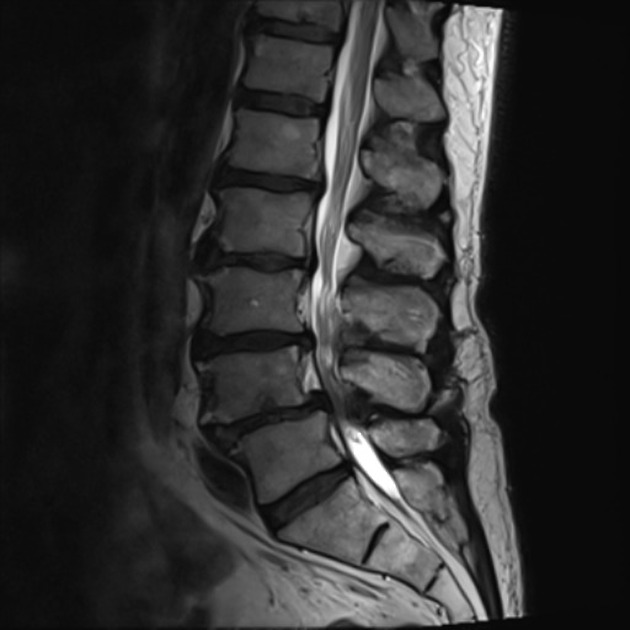

Spinal stenosis, omurilik üzerinde (central stenosis) veya sinirler üzerinde (lateral stenosis) aşırı baskı ile sonuçlanan omurga kanalı içerisindeki daralmadır. Spinal stenosis boyun ve belde meydana gelebilir.